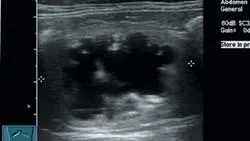

ImagingAbdominal radiographs showed small irregular kidneys (Figure 1, right: Radiograph of the right lateral abdomen. The kidneys are small and irregularly shaped. Mineral densities are visible in the left kidney. View larger image), and irregular margins were evident in ultrasound imaging (Figure 2, below: Ultrasound of the left kidney demonstrating irregular margins. View larger image).